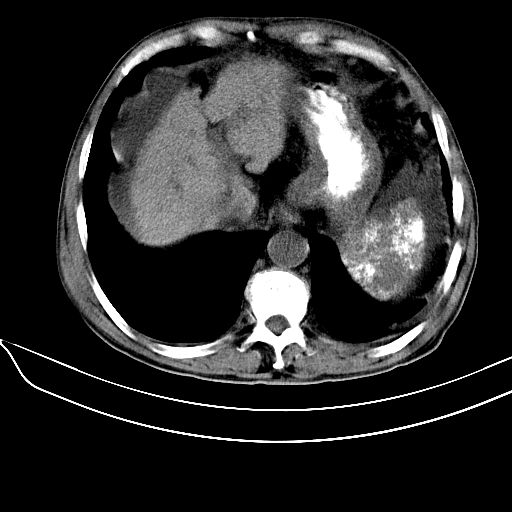

考虑:1、肝硬化、腹水;

2、门脉主干壁钙化(血吸虫所致);

3、脾广泛钙化(原因同上);

肝硬化、腹水; 门脉主干壁钙化,脾广泛钙化;首先考虑血吸虫所致.

1.肝硬化并腹水,2。肝内多发低密度影,肝内胆管扩张?建议增强。3。胆囊颈部条形高密度影,结石?4。脾脏广泛钙化,门脉主干壁钙化,考虑感染所致。